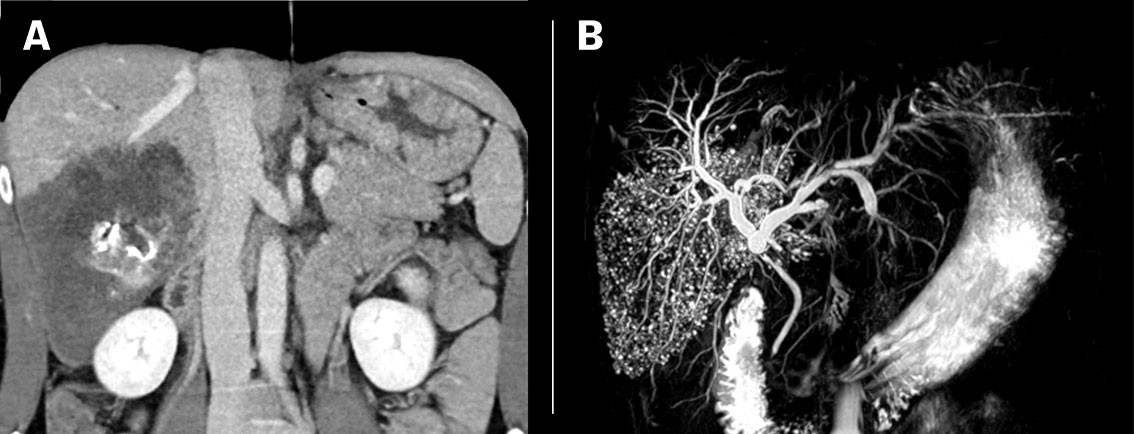

Pasient 2: En mann i 60-årene fra Øst-Europa som har bodd i Norge i mange år, fikk under utredning av en nydiagnostisert tarmkreft påvist en 3 cm stor lobulær lesjon i leversegment 7 ved CT abdomen. Lesjonen ble oppfattet som hemangiom. Ved CT-kontroll ett år senere hadde lesjonen vokst til 6,5 cm, og man mistenkte først metastase, men MR-undersøkelse av leveren avdekket overraskende multiple små cyster (figur 3). Serologi påviste antistoffer mot E. multilocularis. Pasienten startet med albendazol og ble operert med høyresidig hemihepatektomi. Operasjonspreparatet inneholdt en stor multicystisk tumor (figur 4). Histologiske funn var typiske for alveolær ekinokokkose (figur 5). Pasienten utviklet moderat økte levertransaminaser, og albendazol ble midlertidig seponert. Etter flere forsøk på reintroduksjon, ble albendazol endelig seponert syv måneder etter operasjon. Vi planlegger halvårlige kontroller i flere år med radiologi og serologi med tanke på eventuelt residiv.

Diagnostikk ved alveolær ekinokokkose baseres på en kombinasjon av typiske radiologiske funn og positiv serologi. Endelig diagnose stilles ved histopatologisk undersøkelse og/eller PCR-analyser av operasjonsmateriale. Alveolær ekinokokkose klassifiseres radiologisk etter funn på CT (Alveolar Echinococcosis Ulm Classification for Computed Tomography, AEUC-CT) og MR (Kodamas klassifikasjon) (3, 4). På CT fremstår forandringene ofte som uskarpt avgrensete lobulerte oppfylninger med uregelmessig sentral nekrose og spredte forkalkninger suspekt på malign tumor, mens de karakteristiske mikrocystiske komponentene fremkommer tydeligere på MR (figur 1 og 3). MR egner seg best for karakterisering samt lokoregional utbredelse. Diagnosen stilles vanligvis ikke basert på bildediagnostikk alene, da flere andre fokale leverlesjoner, inklusive premaligne og maligne tumorer, kan ha lignende karakteristika (5). FDG PET er nyttig ved initial diagnostikk, samt for postoperativ monitorering og ved mistanke om residiv (6).